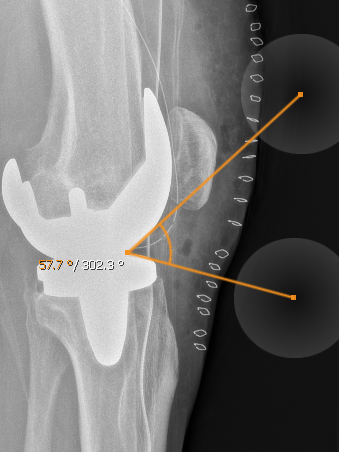

11.1.5. Angle tools

The angle tools allows you to create an angle in the current image slice. The angles lines are adjustable in their length and direction so that you can modify the angle by your needs. You can move the whole angle by tap and hold the intercept point. The angle can be deleted from the annotation menu.

Beside the normal angle tool there is the remote angle. While the normal angle is a real angle, the remote angle calculates the angle between two lines without a crossing point. Beside that, it can be used like the normal angle tool.